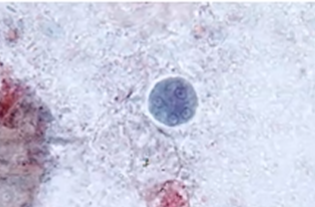

What is the species seen in this photo and WHY?

Entamoeba histolytica/Dispar CYST. Cysts to not eat RBCs and it is very rounded with multiple nuclei. (cannot differentiate bc no RBCs)